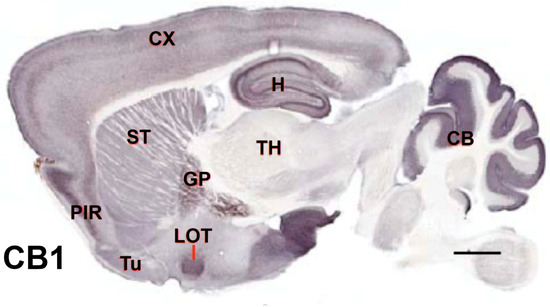

1.3. CB1 Receptor—Localization and Function